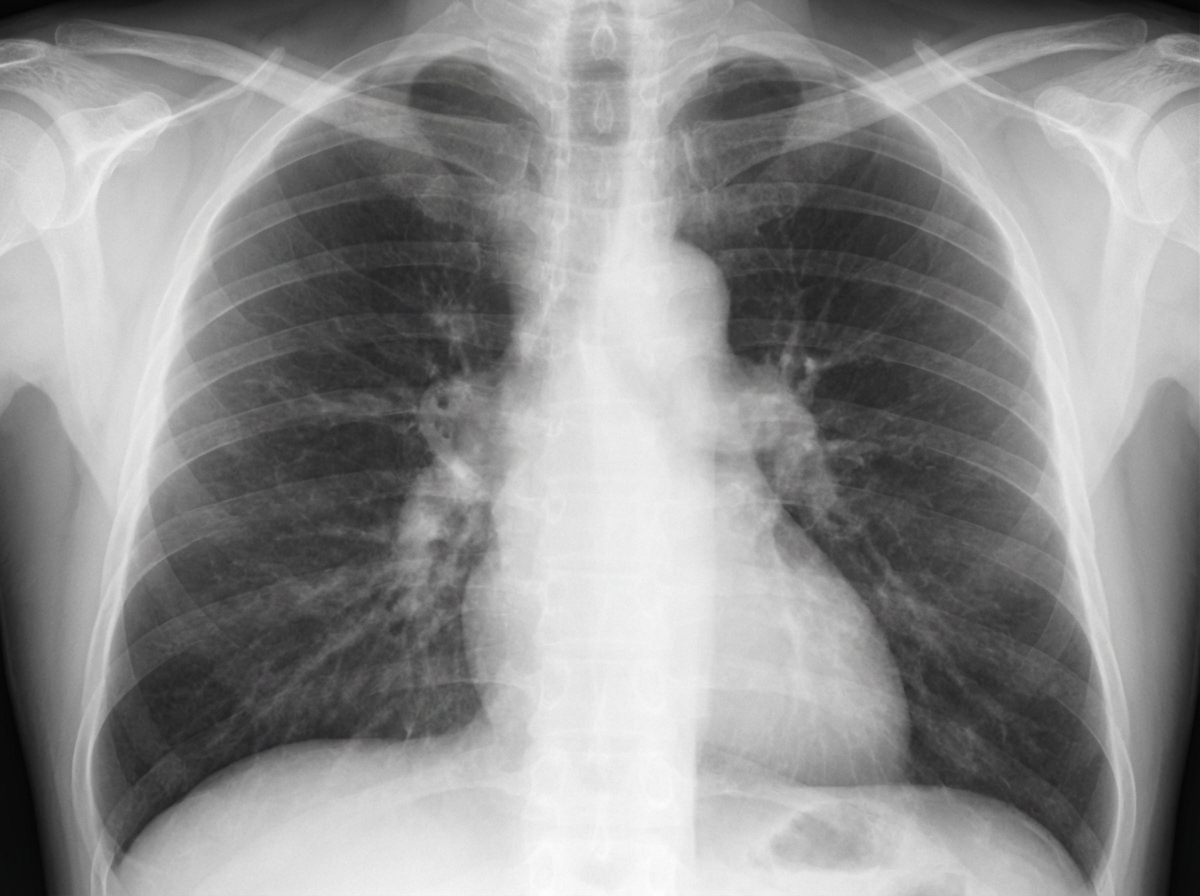

- Metastases: More common than primary lung cancer. Typically multiple, spherical, bilateral nodules.

⭐ Common primary sites for "cannonball" metastases include renal cell carcinoma and choriocarcinoma.